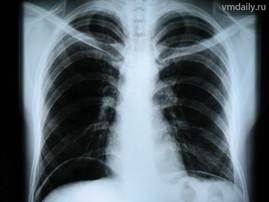

Обзорная рентгенография органов грудной клетки в прямой и боковой проекциях позволяет диагностировать изменения скелета (переломы ребер), инфильтративные и очаговые изменения в легочной ткани, наличие жидкости в плевральной полости (гидроторакс), изменение размеров и формы тени сердца и крупных сосудов и другие патологические состояния (рис. 3).

Рис. 3. Проведение рентгенографии грудной клетки (А), рентгенограммагрудной клетки в прямойпроекции (Б)